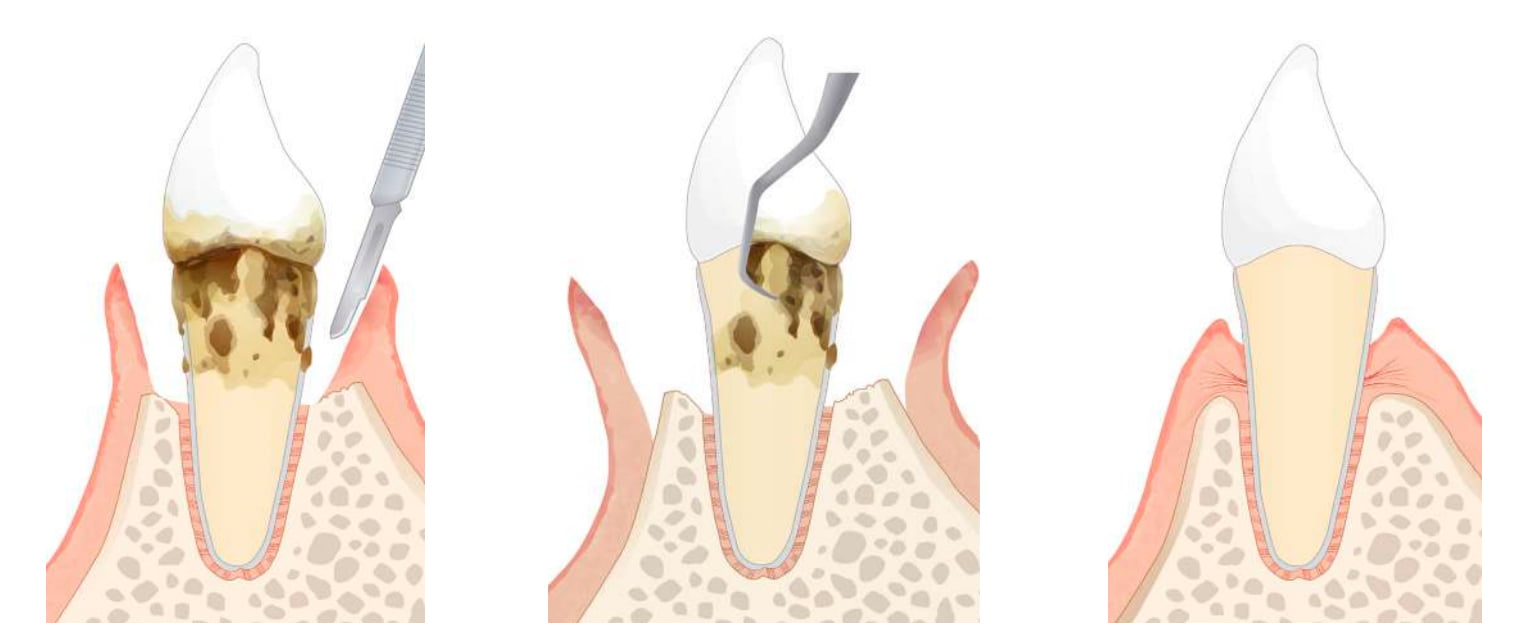

歯周外科処置

歯周外科治療

歯石が歯周ポケットの深いところに入り込んでいる場合には、外科的治療を行うことがあります。

FOP(歯肉剥離掻爬術)

なるべく侵襲を少なく歯周病菌の除去を行う一般的な歯周外科処置

APF(歯肉弁根尖側移動術)

徹底した歯周病菌の除去や歯周ポケットの除去を目的とした切除療法